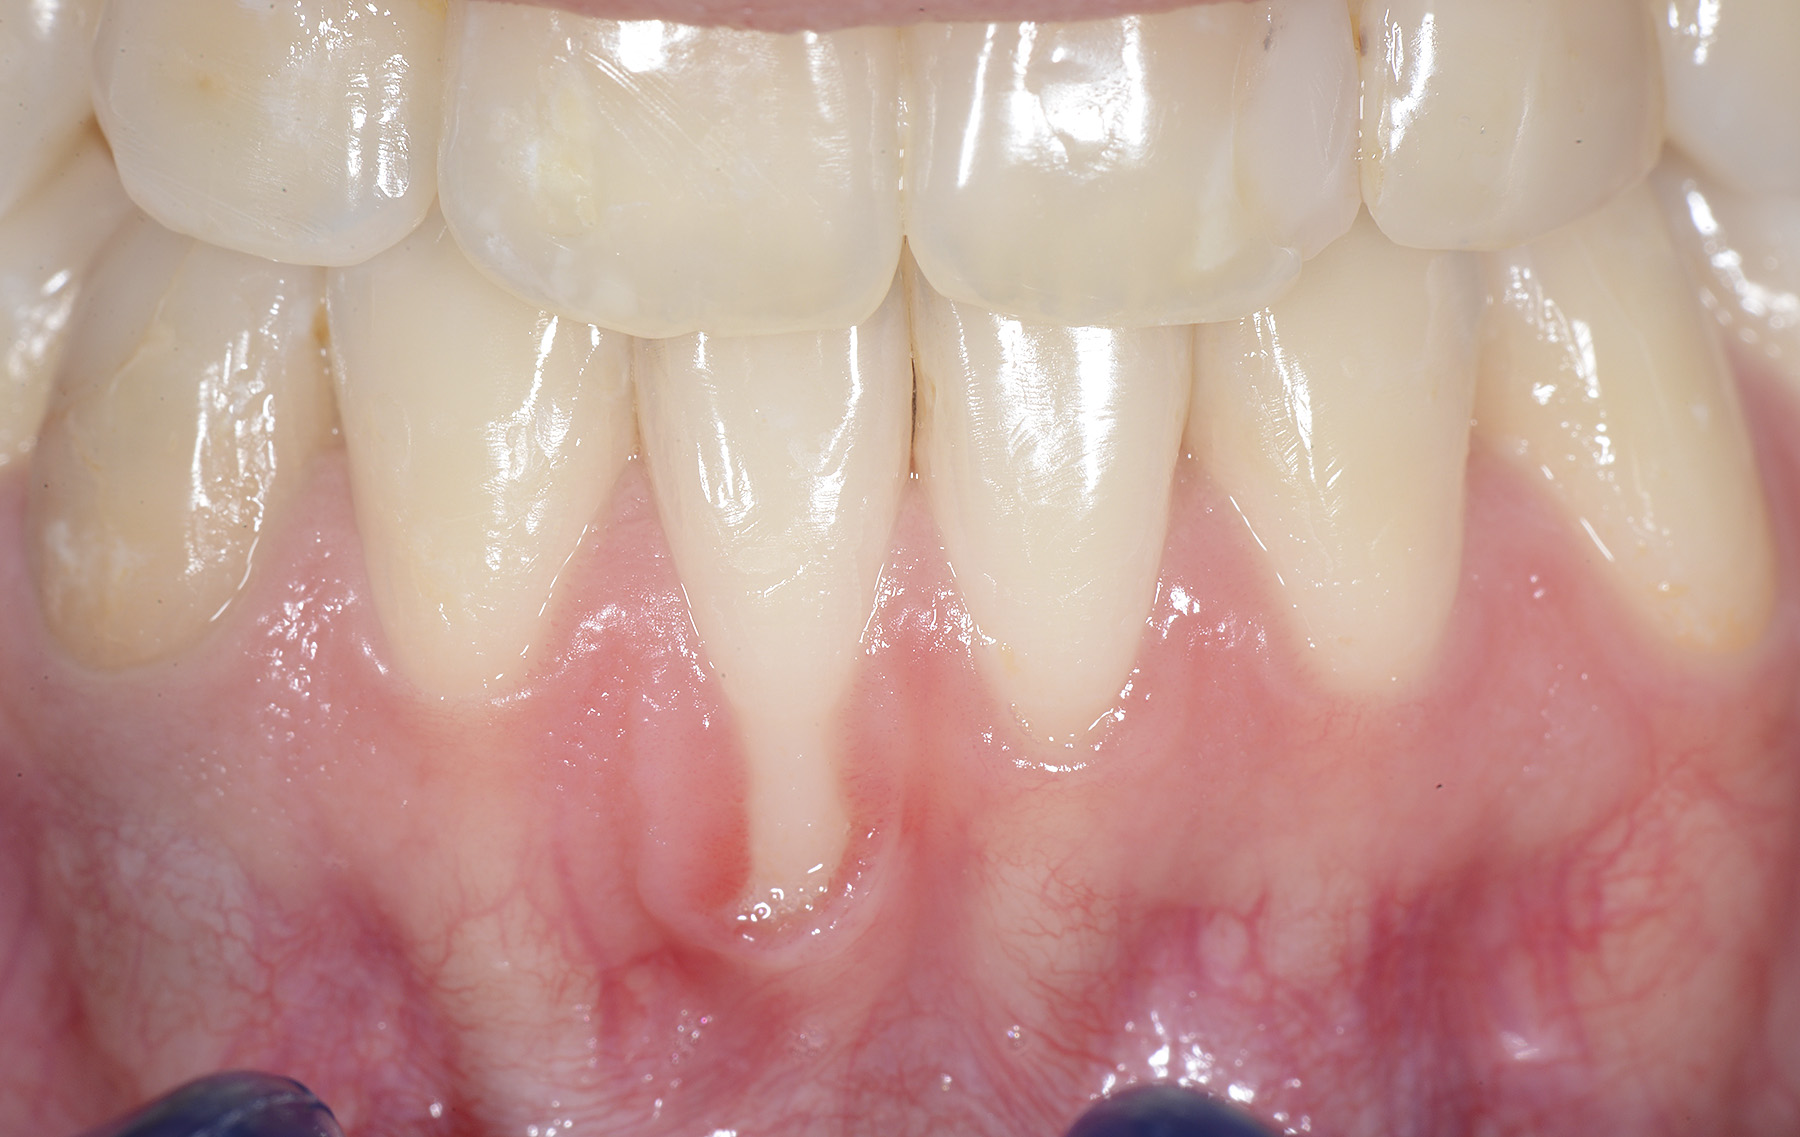

PREMESSA: in seguito all’estrazione dell’incisivo laterale superiore di destra, resasi necessaria per cause batteriche, si decide di affrontare il caso con il posizionamento di un impianto in sostituzione dell’elemento mancante dopo guarigione del sito infetto. Con tecniche rigenerative sia dei tessuti ossei mancanti a causa dell’infezione pregressa, sia dei tessuti gengivali che appaiono inizialmente troppo spostati in alto, si ripristina una corretta morfologia delle parabole (contorni) gengivali e delle papille interdentali (triangoli di gengiva tra due denti vicini).